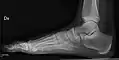

- پا / انگشتان پا - Dorsoplantar، مایل و جانبی[18]

پا راست نرمال به وسیله پروجکشن dorsoplantar

پروجکشن مایل

پروجکشن جانبی